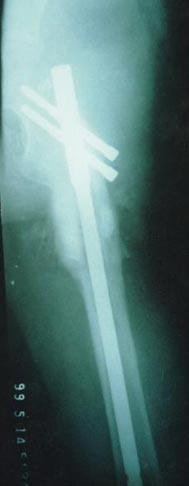

以上图片为三位患者的X线片,显示股骨粗隆下骨折、骨不连,内固定已经失败。

主要采用股骨重建髓内钉获得良好早期的稳定性,为骨愈合创造条件,